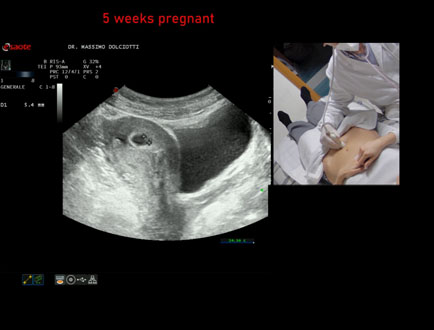

Data inserimento: 06/02/2026

Ecografia del: 28/01/2025

Strumento: Esaote MyLab Eight

Sonda: Convex Multifrequenza 1-8 MHz

Età Paziente: F 28 anni

Motivazione dell'esame: amenorrea.

Commento all'esame: le immagini ed il video documentano la camera gestazionale delle dimensioni di 11 mm e presenza di embrione delle dimensioni di 4,1 - 5,4 mm, con iniziale battito cardiaco.

Conclusioni: gravidanza alla quinta settimana di gestazione (pregnancy in the 5th week of gestation).

In collaborazione: Dr.ssa Marica Manfredi - Ancona, Dr. Ilir Qose - Ancona

Presentazione: Dr. Massimo Dolciotti - Ancona

Elaborazione digitale: Andrea Dini - Ancona